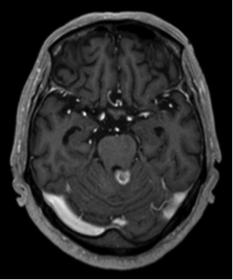

1.髄膜腫

原発性脳腫瘍で最も多い腫瘍ですが、脳そのものから発生するのではなく、脳を包んでいる髄膜から発生します。一般的には良性腫瘍ですが、まれに悪性のこともあります。大きくなると頭痛や麻痺などの症状が出ますが、症状がなくてCT・MRIなどの検査で偶然見つかる場合もあります。小さい場合は経過観察することが多いですが、大きい場合は手術が必要になります。また手術で取り切れない場合や、部位的に摘出困難な場合はサイバーナイフ・トモセラピーによる定位放射線治療を行う場合もあります。

手術後